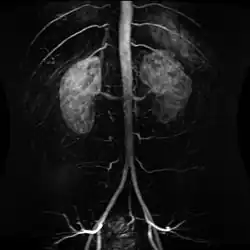

Contrast enhanced MRA of the abdominal aorta demonstrating normal paired arteries.